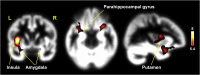

Results: Our study revealed a relationship between sexual function and morphological changes in postmenopausal women. Compared with premenopausal women, the postmenopausal group showed significantly lower brain activations in the major parts of the limbic system and basal ganglia, including the parahippocampal gyrus, head of caudate nucleus, insula, putamen, hippocampus, hypothalamus, amygdala, and globus pallidus, which are involved in sexual behavior and emotional responses. In morphometric analyses, postmenopausal women showed significantly decreased gray matter volumes of the insula, putamen, parahippocampal gyrus, amygdala, and anterior cingulate gyrus, most of which were associated with decreased functional activity during visual sexual arousal in postmenopausal women. In addition, the premenopausal group alone showed a positive correlation between the activity of the insula and the level of estradiol (Pearson correlation r = 0.588; P = .008).